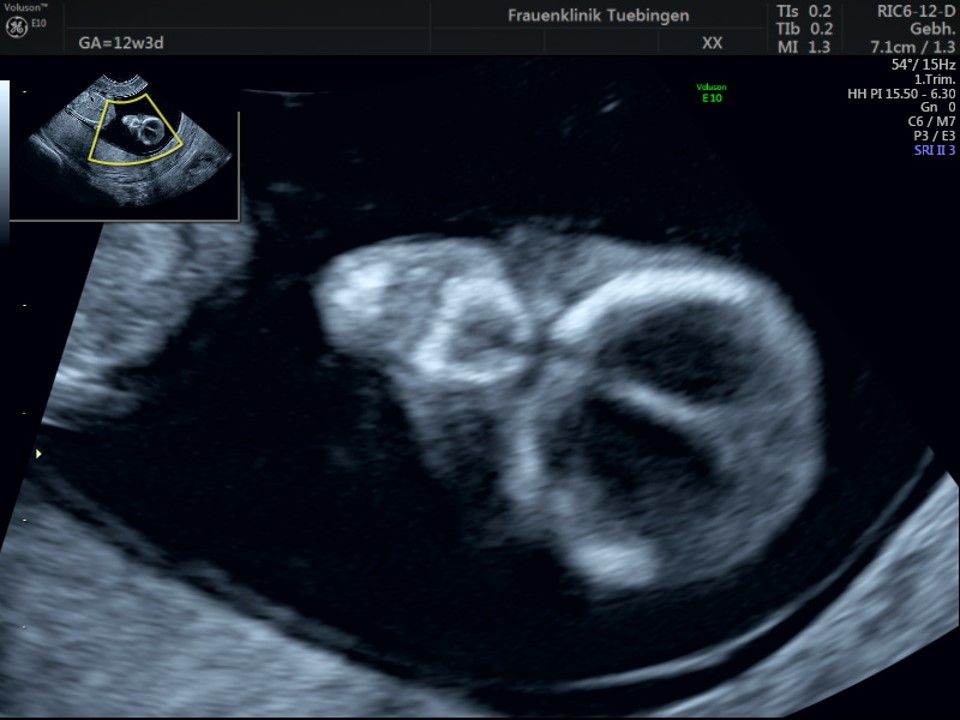

Im Rahmen des Ersttrimester-Screenings untersuchen wir die Organe des Feten mittels Ultraschall. Dabei machen wir auch gerne ein Bild für Sie.

Obwohl der Fet zu diesem Zeitpunkt erst zwischen 5 und 8cm groß ist, lassen sich bereits etwa die Hälfte aller schwerwiegenden Fehlbildungen erkennen bzw. ausschließen. Sollten wir eine Auffälligkeit sehen, werden wir mit Ihnen den Befund und das weitere Vorgehen ausführlich besprechen.

Fetale Anatomie